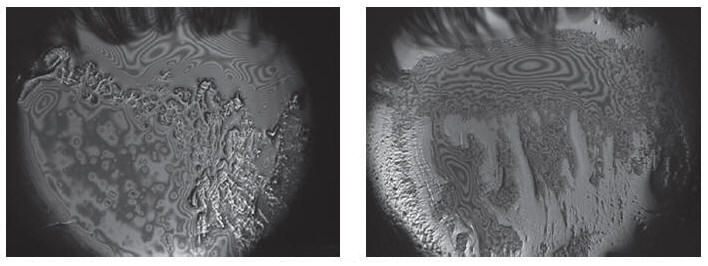

Мейбография -

Мы проводим этот тест с помощью кератотопографа в инфракрасном свете или белом свете, оцениваем каждое веко отдельно после фоторегистрации  по специальной шкале для определения тяжести  дисфункций мейбомиевых желез и  оценки эффективности терапии.

Интерферометрия слёзной пленки

Технология позволяет оценить  полноценность  липидного слоя слёзной пленки, предохраняющего  слезу от избыточного испарения.

Процедура не инвазивна и длится менее пяти минут.

Процедура требует подготовки:   (отказ от косметики и использования крема, мази на кожу век  за двое суток до тестирования), отказ от  ношения  контактных линз в течение двух суток перед обследованием, не тереть глаза непосредственно перед обследованием .